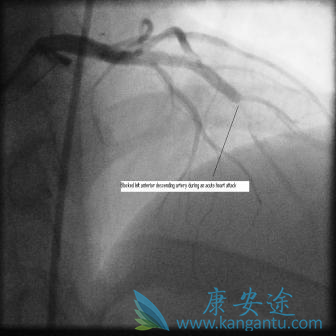

血管成形术和支架通常作为治疗稳定性心绞痛或紧急作为心脏病发作后的突发程序,以打开突然阻塞的动脉(下图)。

在心脏病发作(标签和箭头)和右侧,在“主要”血管成形术和支架之后阻塞血液超过阻塞的左前降支动脉,血管外流动性好